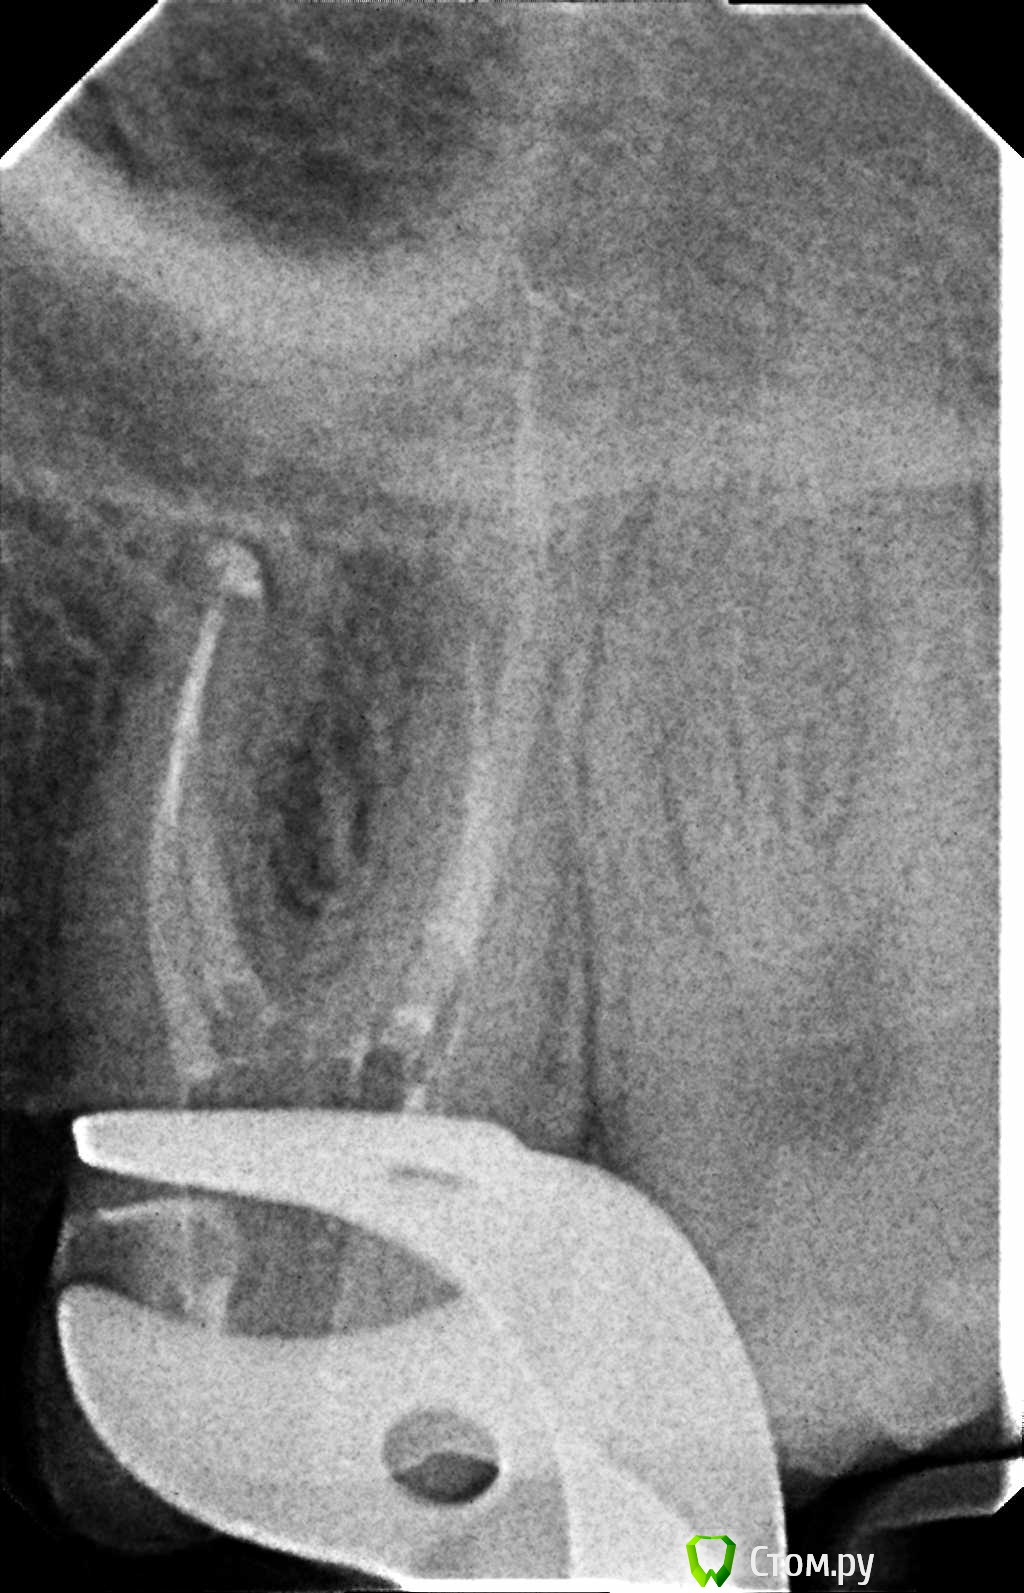

Hans85 Опубликовано 10 января, 2014 Автор Поделиться Опубликовано 10 января, 2014 (изменено) .Новый кейс-совсем свежий пока без долгосрочного результата.Пациентка попала случайно удаляла зуб 28 и хирург сделал ОПТГ,где стали видны обширные периапикальные процессы в области 37 47.Побывав у меня на консультации и услышав план лечения и стоимость,пациентка решила видимо полечить подешевле.,побывав на консультациях в нескольких клиниках и в итоге даже попала к главному стоматологу нашей области. Все ей сказали что удаление онли. Вернулась,-засада была в том что план я писал исходя из ОТПГ не сделав прицел(виноват),сделав прицел понимаю что все сложнее чем я думал-ну что же тем интереснее.Переписав план лечения и подняв ценник на 40%(пациентке не оставалась выбора),начали лечение.1-посещение-ревизия пломбы.понимаю что кто то до меня с маниакальным упорством пытался запломбировать мезиальный язычный канал каналонаполнителями. Убрал два фрагмента из верхней трети мезиального язычного.2-посещение еще фрагмент из мез язычного плюс немного с дистальными поработал(их оказалось два сплит в верхней трети)3-визит обошел фрагмент в мезиальном щечном и доработал остальные каналы.4-визит -паковка.На предпоследнем снимке видны поры-допаковал(просто на финальном не очень видно) Изменено 10 января, 2014 пользователем Hans85 Ссылка на комментарий